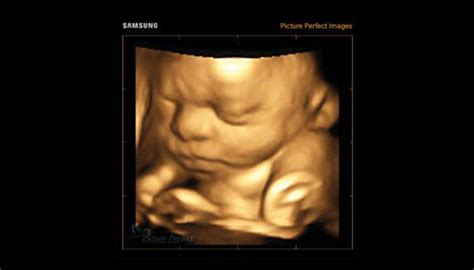

Sarcina este o călătorie extraordinară, marcată de transformări profunde atât pentru mamă, cât și pentru copil. De la primele săptămâni de la concepție, micuțul organism se dezvoltă cu o viteză uimitoare, formându-și sistemele și organele esențiale. Urmărirea atentă a acestei evoluții, pe săptămâni și luni, oferă o perspectivă fascinantă asupra miracolului vieții.

Perioada de început a sarcinii este critică pentru formarea fundamentală a bebelușului. După fertilizare, ovulul devine zigot și începe să se dividă rapid, formând morula, apoi blastocistul, care se implantează în mucoasa uterină. Până în săptămâna a 12-a, se vorbește despre embrion, o etapă în care se pun bazele tuturor sistemelor corporale majore și a organelor esențiale.